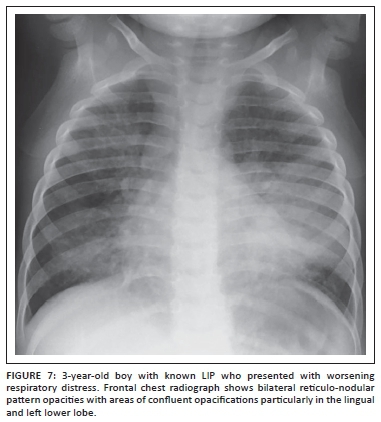

LIP most commonly causes diffuse often symmetrical reticulo-nodular pattern opacities on chest radiographs and CT (Figure 6).5,10,18 The nodules may coalesce to produce areas of confluent airspace opacification (Figure 7).11 Peribronchial thickening alone or cysts and bronchiectasis in long-standing disease may also occur.10,19 Although lymphadenopathy may present in pediatric patients with LIP, it rarely causes tracheobronchial compression which can be often seen in the setting of TB infection.19 It is often difficult to distinguish between LIP and miliary TB on imaging alone. Parotid enlargement as a result of lymphoepithelial cysts, hepatosplenomegaly and digital clubbing are more common in LIP. On HRCT, which may improve the diagnostic accuracy, characteristic perilymphatic and subpleural nodules are often present in pediatric patients with LIP.15